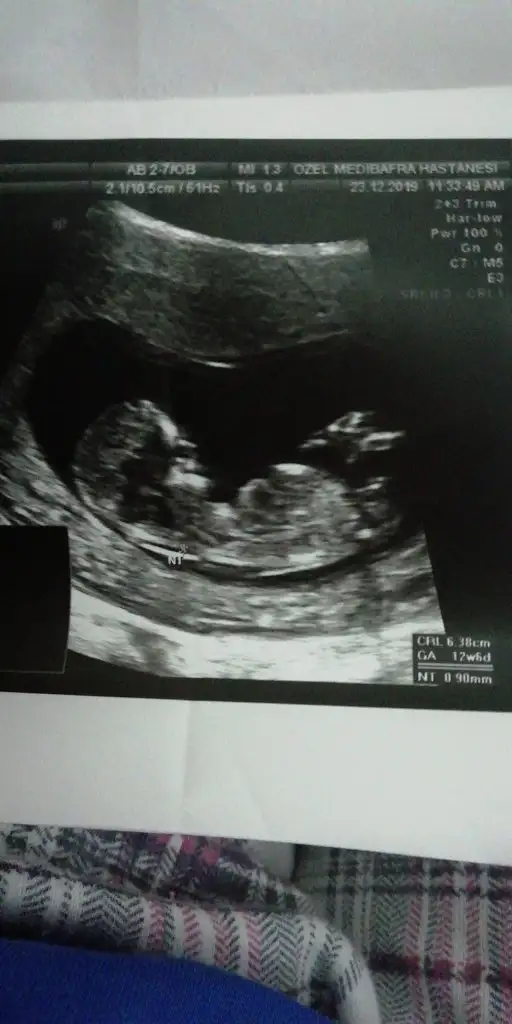

dr soylemeden siz gorun genital nub teorisi ( bebegin cinsiyeti)

Önceki usgmiz 9+3 tü kemk yapısna göre erkek olablir demiştiniz ...sağlıklı olması tek duam...belirtlerme görede herkes erkek diyodu ama ben hep diyodm bu içmdeki kız diye 😍

Saglıkla gelsin minnoş 😊 12 haftasına tahmin etmemişim 😊